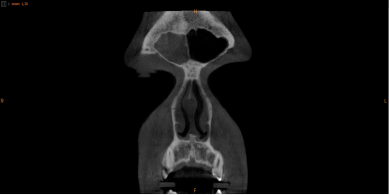

OPIS BADANIA (TOMOGRAFIA ZATOK)

Przewody nosowe niedrożne po stronie prawej. W prawej zatoce szczękowej widoczne pogrubienie błony śluzowej do połowy jej wysokości w zachyłku zębodołowym oraz przyścienne, liniowe zgrubienia 3-6 mm na ścianie przyśrodkowej i bocznej. Kompleks ujściowo-przewodowy po stronie prawej niedrożny. Komórki sitowe przednie, środkowe i tylne – niepowietrzne.

Zatoka czołowa zacieniona po stronie prawej. Prawy przedział zatoki klinowej zacieniony.

Po stronie lewej przyścienne zgrubienia błony śluzowej w świetle zatoki szczękowej. Kompleks ujściowo-przewodowy drożny. Zacienienie obserwowane w komórkach sitowia w odcinku przednim. Pozostałe zatoki po stronie lewej – normogram.